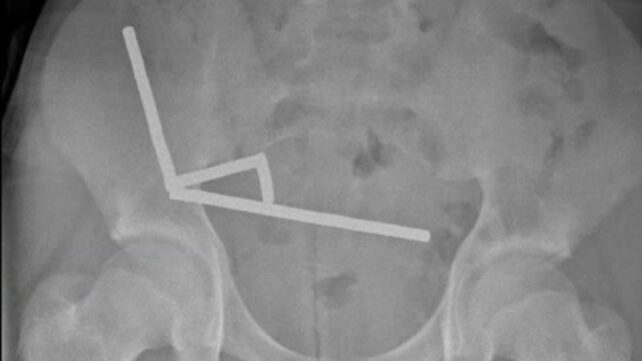

Using an X-ray, doctors imaged four linear chains in separate parts of the boy's bowel.

During surgery, the chains were found in sections of the small bowel and caecum. Squeezing together, they were causing several patches of tissue to die from a lack of blood in what is known as pressure necrosis.